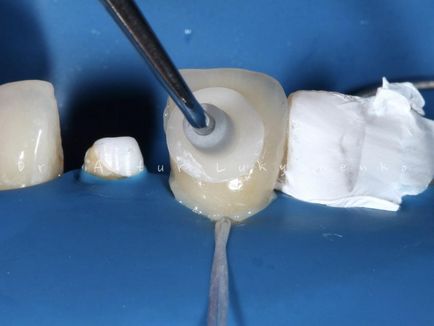

A fénykép 16, 17, 18. Az izolálás után közgát fogak és homokfúvással alumínium-oxid fixáltuk első furnér, majd kerámia koronák.

A fénykép 16, 17, 18. Az izolálás után közgát fogak és homokfúvással alumínium-oxid fixáltuk első furnér, majd kerámia koronák.